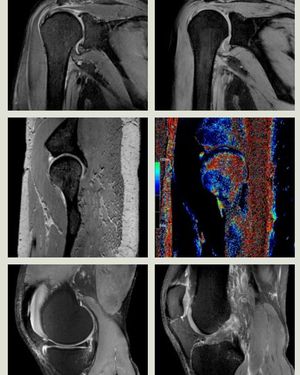

MSK MRI at 7 Tesla!

Mri

Msk

Ultra High Field